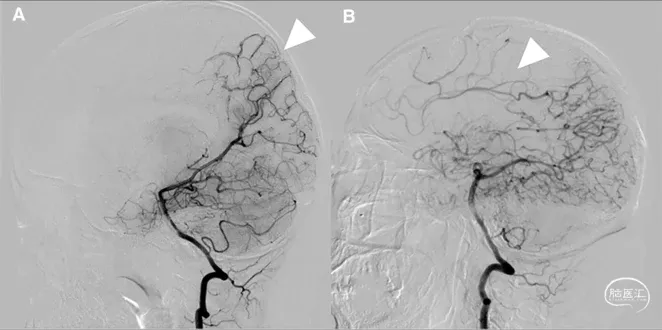

图1 从大脑后动脉(PCA)到大脑前动脉(ACA)的软脑膜侧支;A,椎动脉注射侧位图显示ACA和PCA区域之间的逆行血流(PCA→ACA顶枕支)延伸到皮质边界区;B,经后胼胝体周动脉经中央沟的血供。【7】